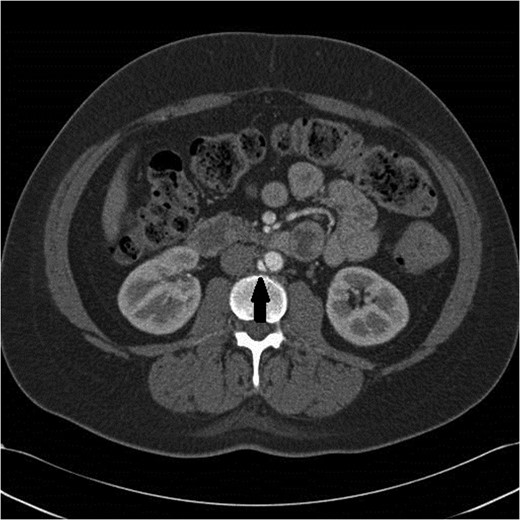

A follow-up CT scan was obtained 3 months later. At the location of the previous aortic abnormality, there was a 3 × 1 cm pseudoaneurysm that had formed and could now be clearly seen (Figs 2 and 3). The patient was asymptomatic.

Black arrow pointing to pseudoaneurysm with enhancing flow outside of the aortic lumen.